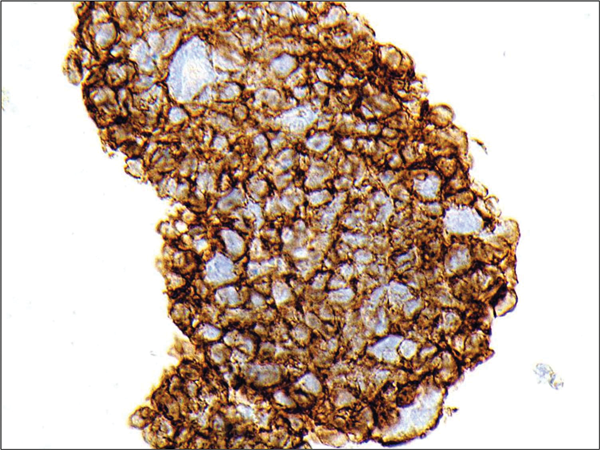

Figure 5: CD56 immunohistochemistry showing strong

circumferential staining with antibodies to N-CAM (CD56).